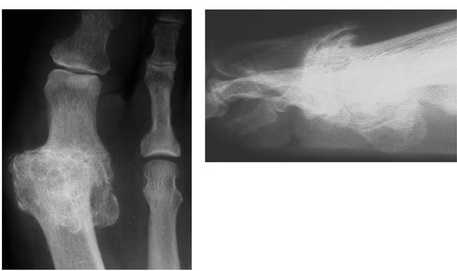

МРТ при тяжелом повреждении связок первого пальца. А, На МРТ видны признаки разрыва связок и смещение сесамовидной кости. В, На МРТ видны признаки полного разрыва медиальной коллатеральной связки при сохранении целостности аналогичной латеральной связки.